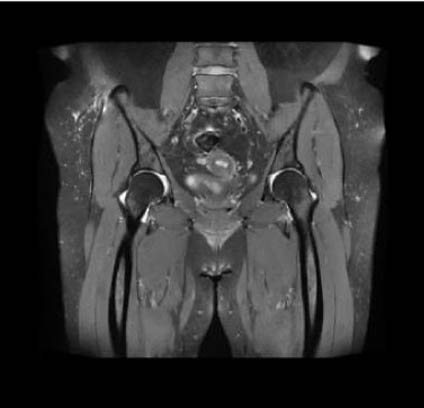

EXCEPTIONAL IMAGE QUALITY

- Best-in-class homogeneity and gradient performance

- World’s largest field of view (60x60x50 cm)

- Motion insensitive sequences for clearer images